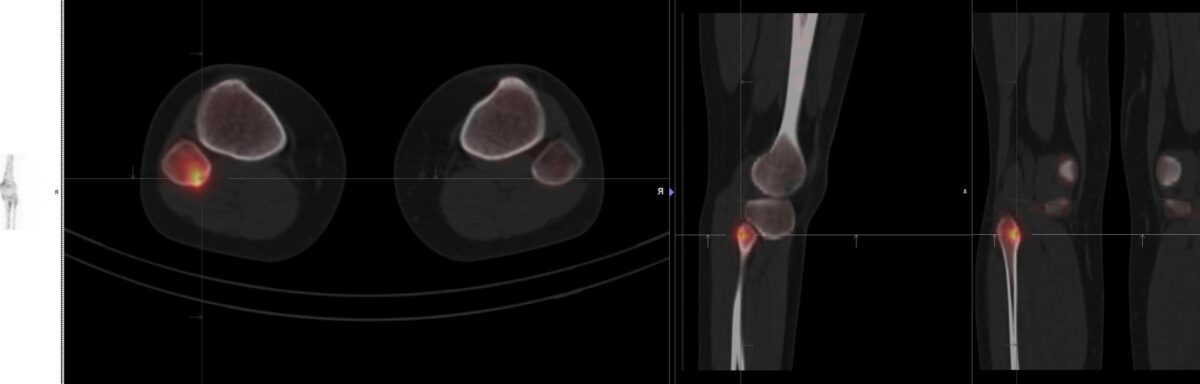

La scintigraphie osseuse est une technique d’imagerie médicale nucléaire incontournable dans l’évaluation et le diagnostic de nombreuses pathologies squelettiques. En particulier, lorsqu’il s’agit de l’arthrose, une affection dégénérative touchant les articulations, cette modalité d’examen peut apporter des informations précieuses. La radionucléide utilisée en scintigraphie osseuse se fixe sur les zones où le métabolisme osseux est intensifié, ce qui permet de mettre en évidence les régions atteintes par l’arthrose avec une grande sensibilité. Cette méthode d’imagerie se distingue par son caractère non invasif et sa capacité à réaliser une évaluation globale du squelette, offrant ainsi une vue d’ensemble qui peut échapper à d’autres techniques plus localisées comme la radiographie ou l’IRM (Imagerie par Résonance Magnétique). En outre, la scintigraphie osseuse permet de suivre l’évolution de l’arthrose ou d’autres maladies osseuses, facilitant ainsi la prise en charge thérapeutique adaptée. Cet examen, qui requiert une expertise soignée pour son interprétation, repose sur l’utilisation de traceurs marqués par des éléments radioactifs, tels que le technétium-99m, assurant ainsi la production d’images scintigraphiques de haute qualité.

L’examen se déroule en deux étapes principales : tout d’abord, un radiotraceur (généralement du technétium-99m) est injecté dans la veine du patient. Ce produit se fixe sur les zones osseuses ayant une activité métabolique élevée, typiques des zones touchées par l’arthrose. Après une période d’attente nécessaire à la fixation du radiotraceur, le patient est placé sous une caméra gamma qui va détecter la radioactivité émise et créer une image des os.

La scintigraphie osseuse est une technique d’imagerie médicale qui permet de détecter les changements dans le métabolisme osseux. Elle utilise des traceurs radioactifs, lesquels sont absorbés par le tissu osseux en fonction de son activité. En cas d’arthrose, des modifications du cartilage et de l’os adjacents peuvent induire une augmentation de l’activité osseuse. La scintigraphie peut donc révéler ces zones d’activité accrue, appelées « hot spots ». Ces informations peuvent aider à confirmer le diagnostic d’arthrose, à évaluer son étendue et à suivre la progression de la maladie.